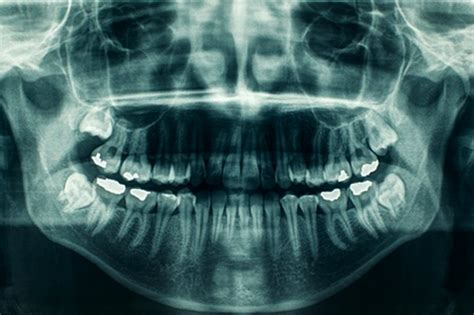

La ortopantomografía, también conocida como radiografía panorámica dental, es una imagen radiológica que muestra una visión general de la boca, incluyendo los dientes, la mandíbula, el maxilar y otras estructuras adyacentes, como los senos paranasales y la articulación temporomandibular. Se trata de una imagen bidimensional plana que facilita una vista panorámica de toda la estructura de la boca. Es una radiografía panorámica que muestra la totalidad de las estructuras orales y que se realiza en un aparato específico denominado ortopantomógrafo.

La ortopantomografía es la radiografía más utilizada por los dentistas, ya que es una gran fuente de información. También, son muy útiles para planificar futuros tratamientos como extracciones dentales, ortodoncia, implantes dentales, etc. Una ortopantomografía proporciona una vista completa de todas las piezas dentales, incluyendo aquellas que aún no han erupcionado completamente. Además de los dientes, una ortopantomografía muestra el estado de las encías y los huesos que sostienen los dientes. Esta radiografía panorámica también ofrece información sobre las estructuras anatómicas adyacentes a la cavidad oral.

- Dientes: La dentición debe mostrar una curva suave en la línea de sonrisa, con un espacio fácil de distinguir entre los dientes superiores e inferiores. Los dientes posteriores deben tener un tamaño normal y no debe existir una superposición excesiva entre los premolares. Los ápices de los dientes anteriores deben estar completos y las coronas deben ser visibles en la imagen radiográfica.

- Senos y nariz: Los tejidos blandos de la nariz y sus cartílagos deben estar claramente visibles en la imagen radiográfica. La sombra del paladar duro debe ser notoria y algunas imágenes fantasmas del paladar pueden ser visibles en los senos maxilares. En la imagen la lengua se debe observar en contacto con el paladar.

- Cóndilos mandibulares: Ambos cóndilos deben aparecer centrados en la imagen radiográfica, con tamaño y altura similares en relación al plano horizontal.

- Rama de la mandíbula y columna cervical: La rama mandibular debe ser similar en ambos lados de la imagen. La columna vertebral, cuando sea visible, no debe estar superpuesta a la rama mandibular y la distancia entre ellas debe ser igual en ambos lados.

- Cuerpo mandibular: La corteza inferior de la mandíbula debe mostrar una imagen uniforme y continua. No deben existir imágenes fantasmas o dobles imágenes del hueso hioides y la línea media de la mandíbula y maxilar no deben estar aumentadas.